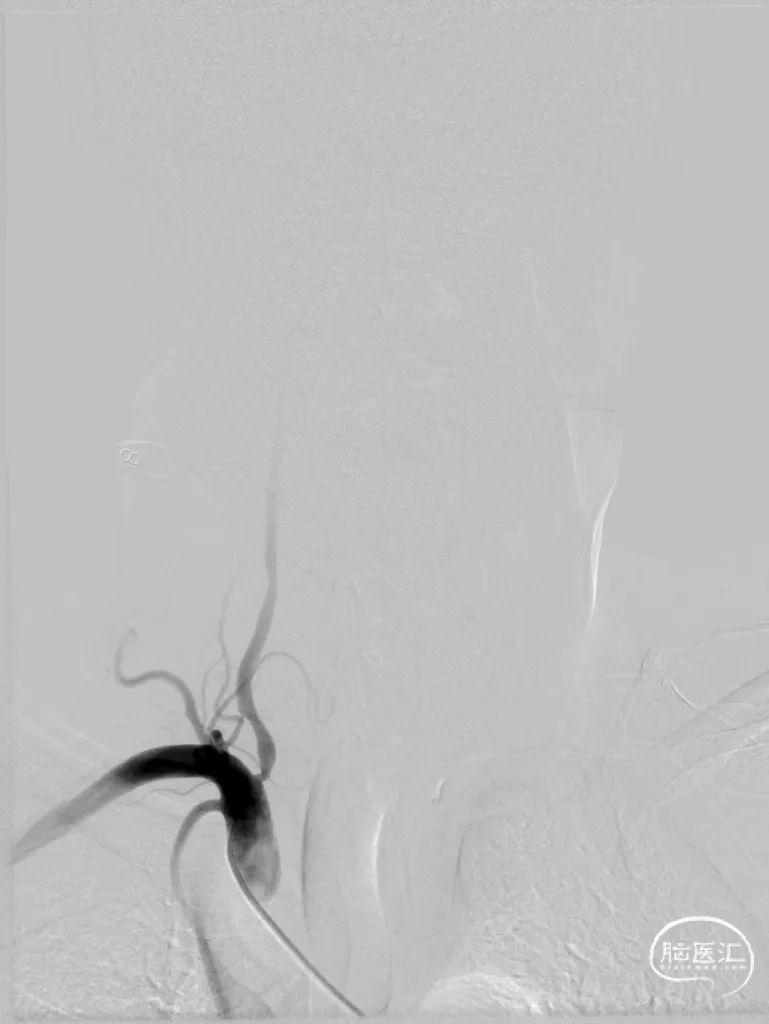

DSA提示:双侧颈内动脉及颅内血管未见明显狭窄,右侧椎动脉优势,左侧椎动脉纤细,V4段闭塞。右侧椎动脉起始处重度狭窄,右椎V4段及基底动脉近端局限性重度狭窄。患者反复间断发作头晕,考虑后循环缺血引起的TIA发作,且强化药物治疗效果不佳,有介入治疗适应症。

手术过程

全麻后,股动脉置入6F血管鞘,6F导引导管配合超滑导丝至右侧锁骨下动脉建立通路,Synchro-14(200cm)微导丝配合4mm×30mm快交球囊定位V1狭窄扩张。

6F导引导管进入V2后,Synchro-14 (200cm)微导丝配合Gateway 2.5mm×9mm球囊先后进行基底动脉、椎动脉V4段狭窄扩张。

撤出球囊后,Synchro-14(200cm)微导丝配合XT-27至基底动脉远端,从远至近分别置入Neuroform EZ 3mm×15mm及Neuroform EZ 3.5mm×20mm支架。

最后保留微导丝在椎动脉内,将导引导管退至锁骨下动脉后,送入5mm×19mm球扩式支架并释放。